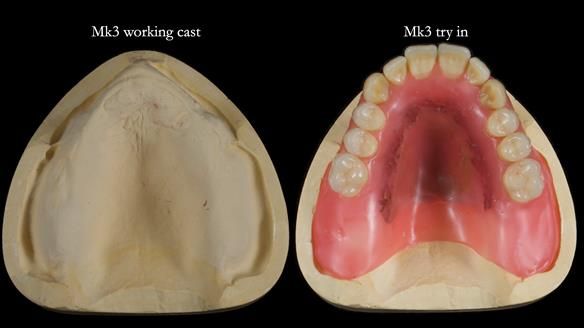

Twelve months after the final extractions, I made the Mk3 definitive complete upper denture.

For the Mk3, we embedded the metal base fully within the fitting surface acrylic. This design allowed adjustment of the polished surface using universal marking spray to fine-tune sibilance and prevented any join between the metal and acrylic from being felt by the tongue.